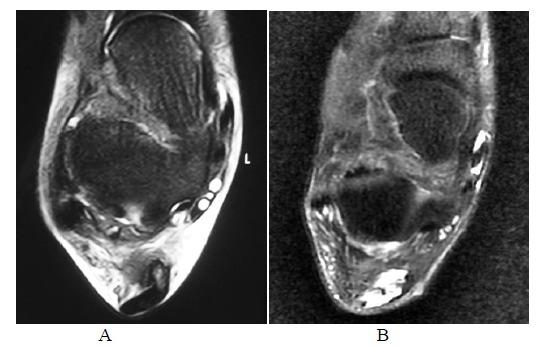

手术修复后跟腱的磁共振成像

MR Imaging of the Achilles Tendon after Surgical Repair.

Achilles tendon tear is common and increasingly frequent. Magnetic resonance imaging (MRI) is the modality of choice for radiological evaluation. It is accurate to assess the status and integrity of the tendon with well documented features. In this article, the MR findings of a normal Achilles tendon as well as common diseases like insertional and noninsertional tendinosis, chronic tendinosis with marked lengthening, tendon rupture are illustrated. After a torn Achilles tendon receives surgical repair, it undergoes different stages of healing process including inflammatory, reparative and remodeling phases. Acute scar tissue in the surgical bed may share similar MR features of tendon re-rupture especially in the early healing phase because both are T2W hyperintense. The size of the gap may even appear larger than expected on T2W images possibly due to tendon remodeling. Understanding of the healing process in post-operative period may prevent overestimation of tendon gap and misdiagnosis of re-tear. We describe the MR features of the post-operative changes with serial studies in different months after surgery. The MR findings with the highlights of the expected sequential changes in normal healing process are illustrated in different cases. A case with surgical repair on a partial tear of Achilles tendon is also included.

摘要

跟腱撕裂很常见且愈发频发。磁共振成像(MRI)是放射学评估的首选方式。它能够准确评估肌腱的状态和完整性,且具有充分记录的特征。在本文中,展示了正常跟腱的磁共振成像表现以及诸如附着点和非附着点肌腱病、伴有明显延长的慢性肌腱病、肌腱断裂等常见疾病的表现。跟腱撕裂接受手术修复后,会经历不同的愈合阶段,包括炎症期、修复期和重塑期。手术部位的急性瘢痕组织可能具有与肌腱再次断裂相似的磁共振成像特征,尤其是在愈合早期,因为二者在T2加权像上均呈高信号。在T2加权像上,间隙大小甚至可能看起来比预期更大,这可能是由于肌腱重塑所致。了解术后愈合过程可避免对肌腱间隙的高估以及对再次撕裂的误诊。我们通过对术后不同月份的系列研究来描述术后改变的磁共振成像特征。在不同病例中展示了磁共振成像表现以及正常愈合过程中预期的连续变化要点。还纳入了一例跟腱部分撕裂手术修复的病例。